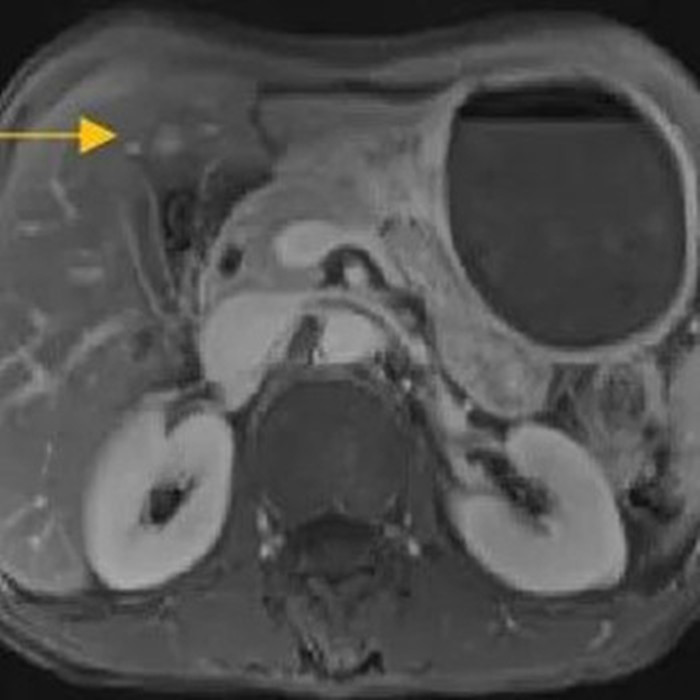

經(jīng)過6個(gè)周期,前后4個(gè)月的治療,周先生再次復(fù)查CT,提示胃部腫瘤,轉(zhuǎn)移的胃旁淋巴結(jié)、肝臟腫瘤都有明顯縮小,營養(yǎng)狀況良好,能正常進(jìn)食,體重增加了6斤,精神狀態(tài)比原先好了很多。

治療后

根據(jù)復(fù)查的CT結(jié)果,金尹和胃外科主任醫(yī)師余春,聯(lián)系了溫州醫(yī)科大學(xué)附屬第一醫(yī)院胃腸外科主任陳笑雷、閆競一團(tuán)隊(duì),對周先生的病情再次進(jìn)行評(píng)估討論,認(rèn)為通過前期的轉(zhuǎn)化治療,效果顯著,建議手術(shù)根治。